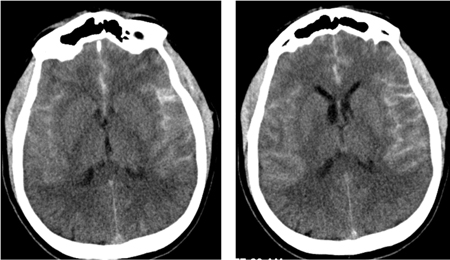

Subarachnoid hemorrhage

CT brain showing subarachnoid hemorrhage from a ruptured posterior cerebral artery aneurysm (1 of 2)

Courtesy of Dr Salah Keyrouz; used with permission